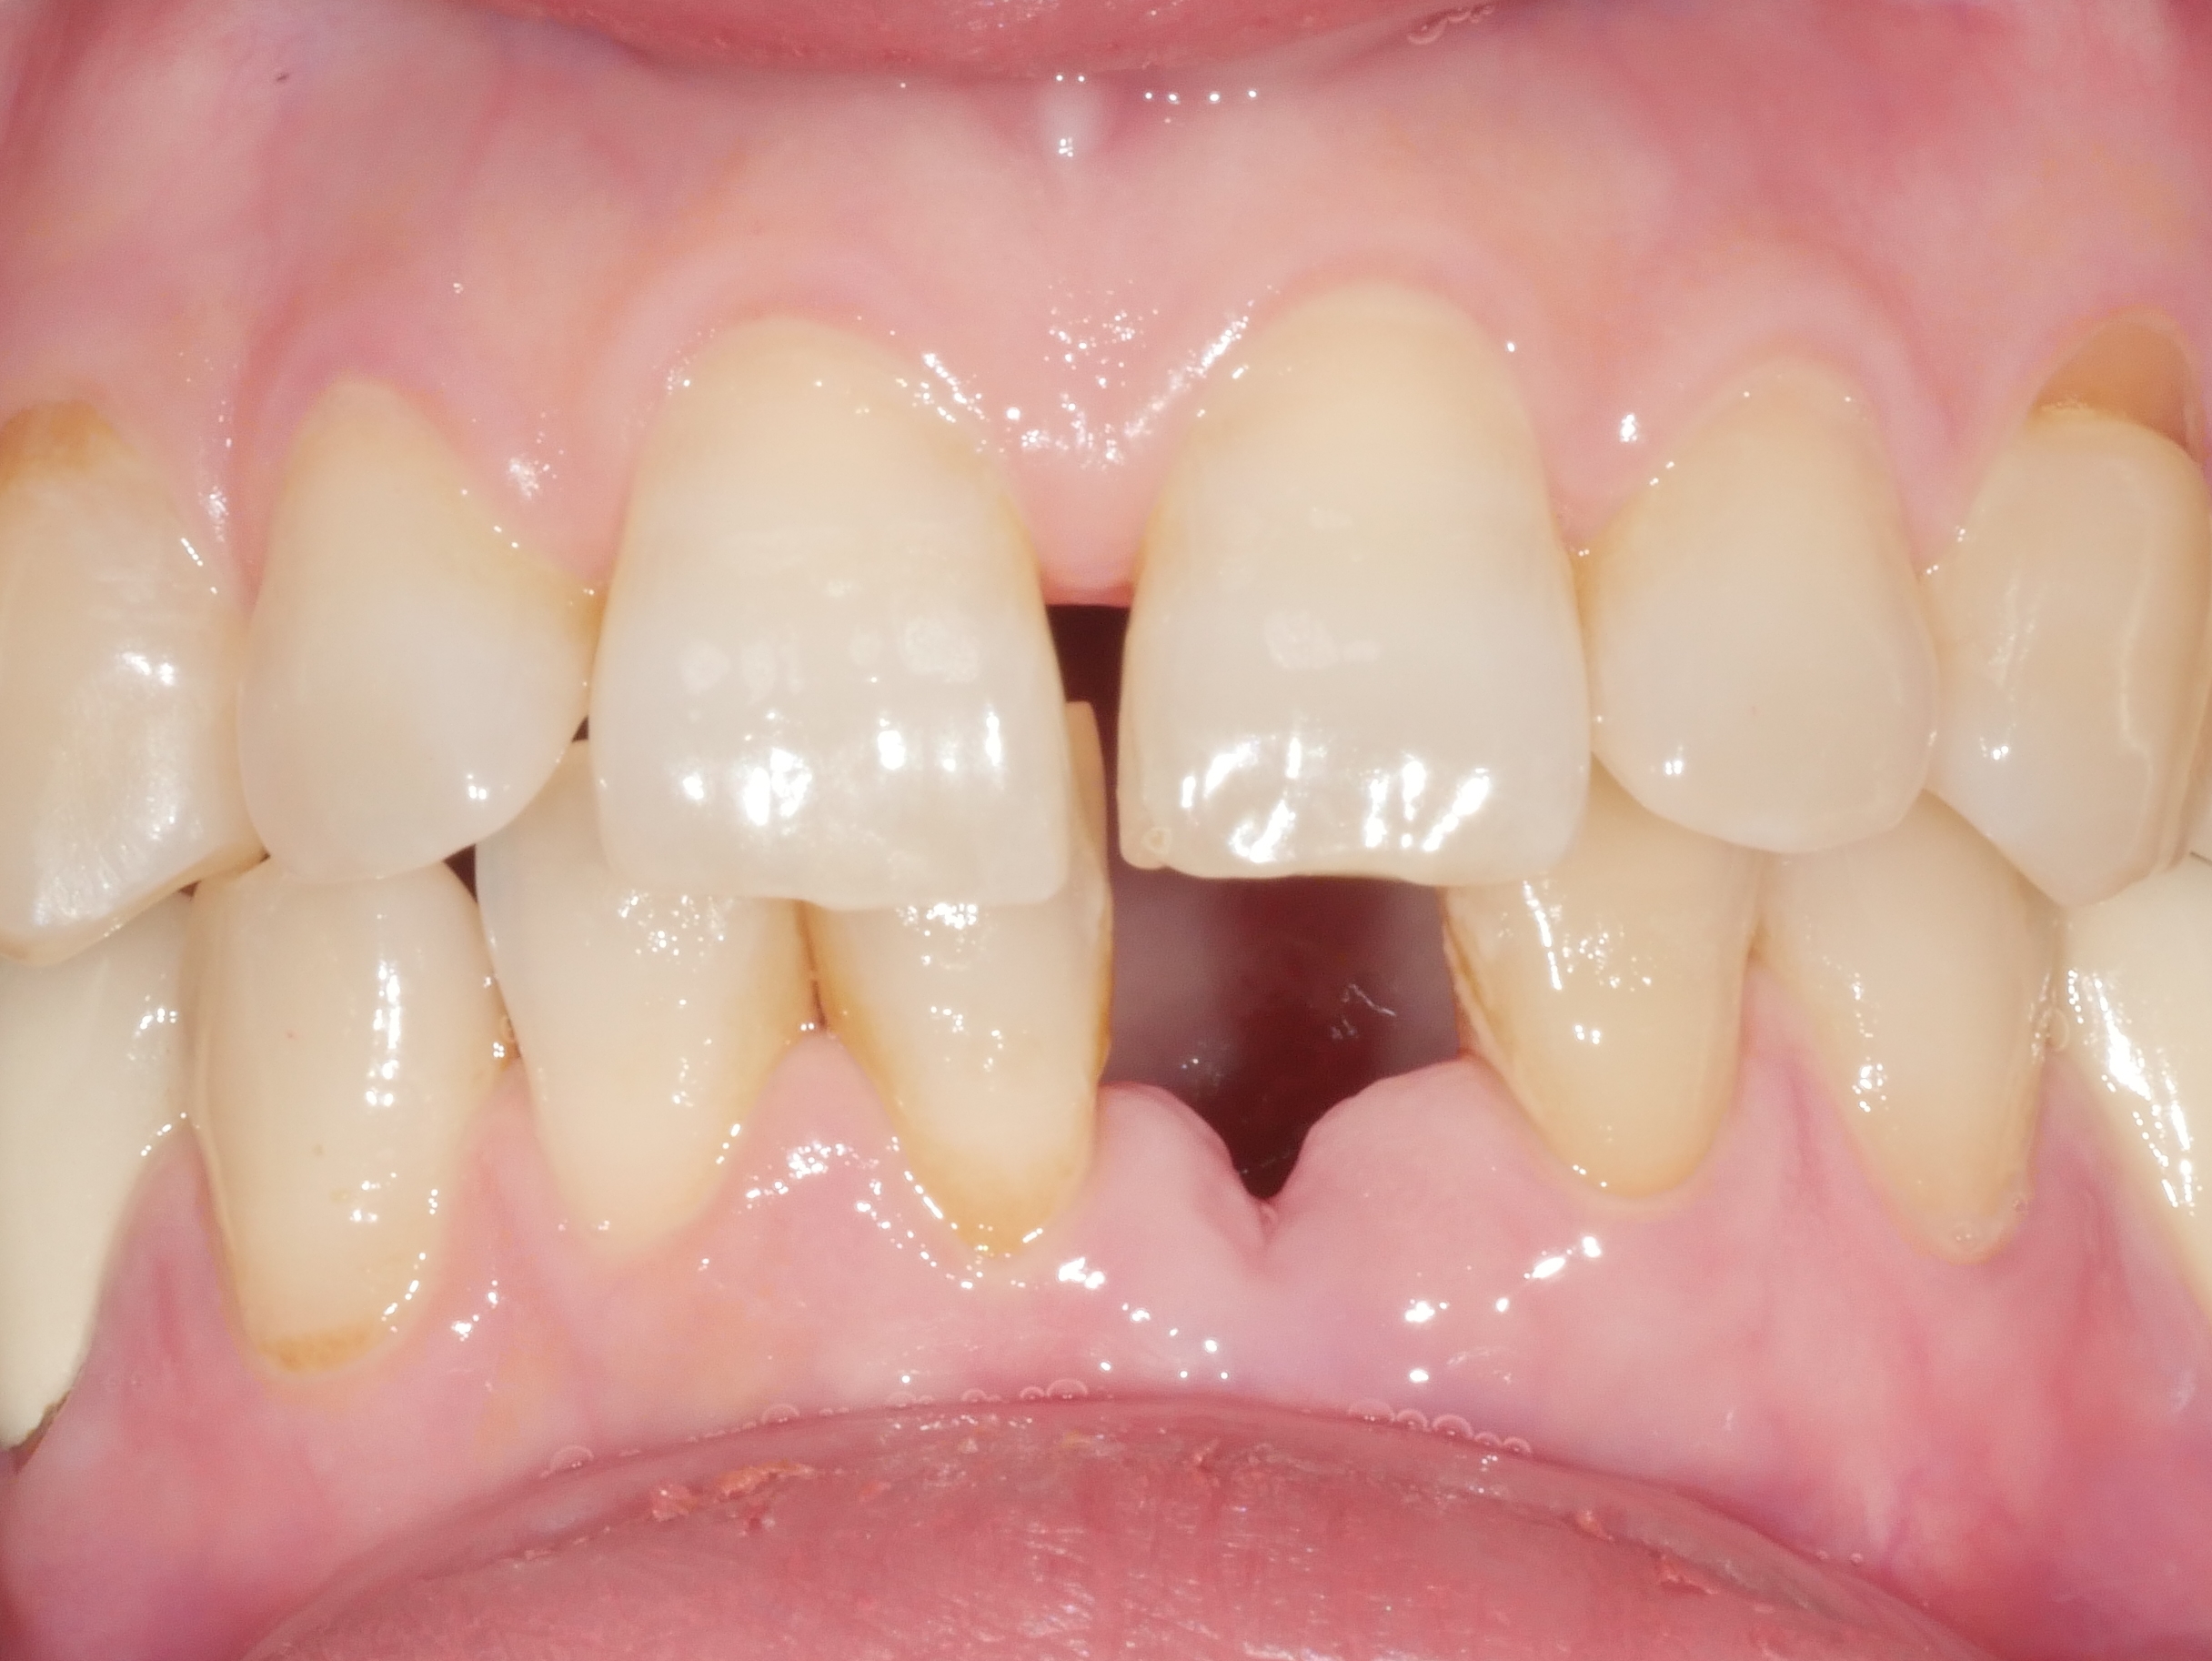

아래 앞니 빠진 부위를 임플란트로 치료

치료전 2025.04.15 / 치료후 2025.09.23